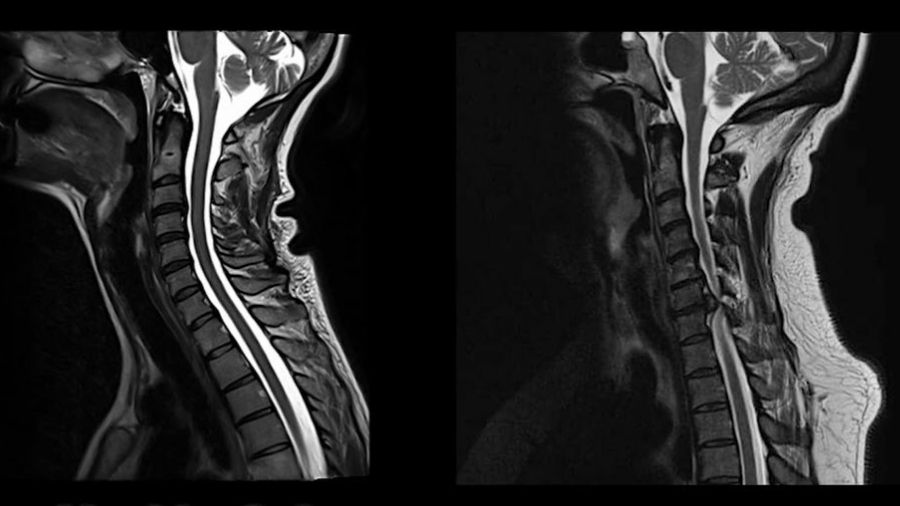

Pioneers in spinal cord neurology and spine surgery, such as Sir Ludwig Guttmann and Charles Elsberg, relied on a detailed neurological examination and patient history while imaging was in its infancy. As a result, patients were more severely impaired when referred to spine surgery. With the dawn of neuroimaging as well as improved access to healthcare, patients are generally referred earlier for MRI in developed countries. MRI is now considered the gold-standard for identifying spinal canal stenosis and detecting structural spinal cord compression. However, given the high prevalence of asymptomatic spinal cord compression [2], poor correlation between imaging findings and disease severity, and a lack of awareness of subtle neurological deficits [3], there is still substantial delay in the diagnosis of DCM and referral to spine specialists.

Advanced neurophysiology and neuroimaging of the spinal cord

Cervical spine imaging, specifically MRI, is essential to confirm a diagnosis of DCM. Although spinal canal narrowing is a prerequisite for DCM, the degree of cervical canal stenosis and cord compression is often not associated with disease severity. Carl Zipser is interested in advanced neurophysiology and neuroimaging of the spinal cord. He contributed to a study that investigated spinal cord motion with MRI and determined that movement and ongoing oscillations are increased at the level of maximum stenosis in patients with DCM [4]. This imaging metric holds promise as a biomarker of mechanical stress to the spinal cord and needs to be further studied.